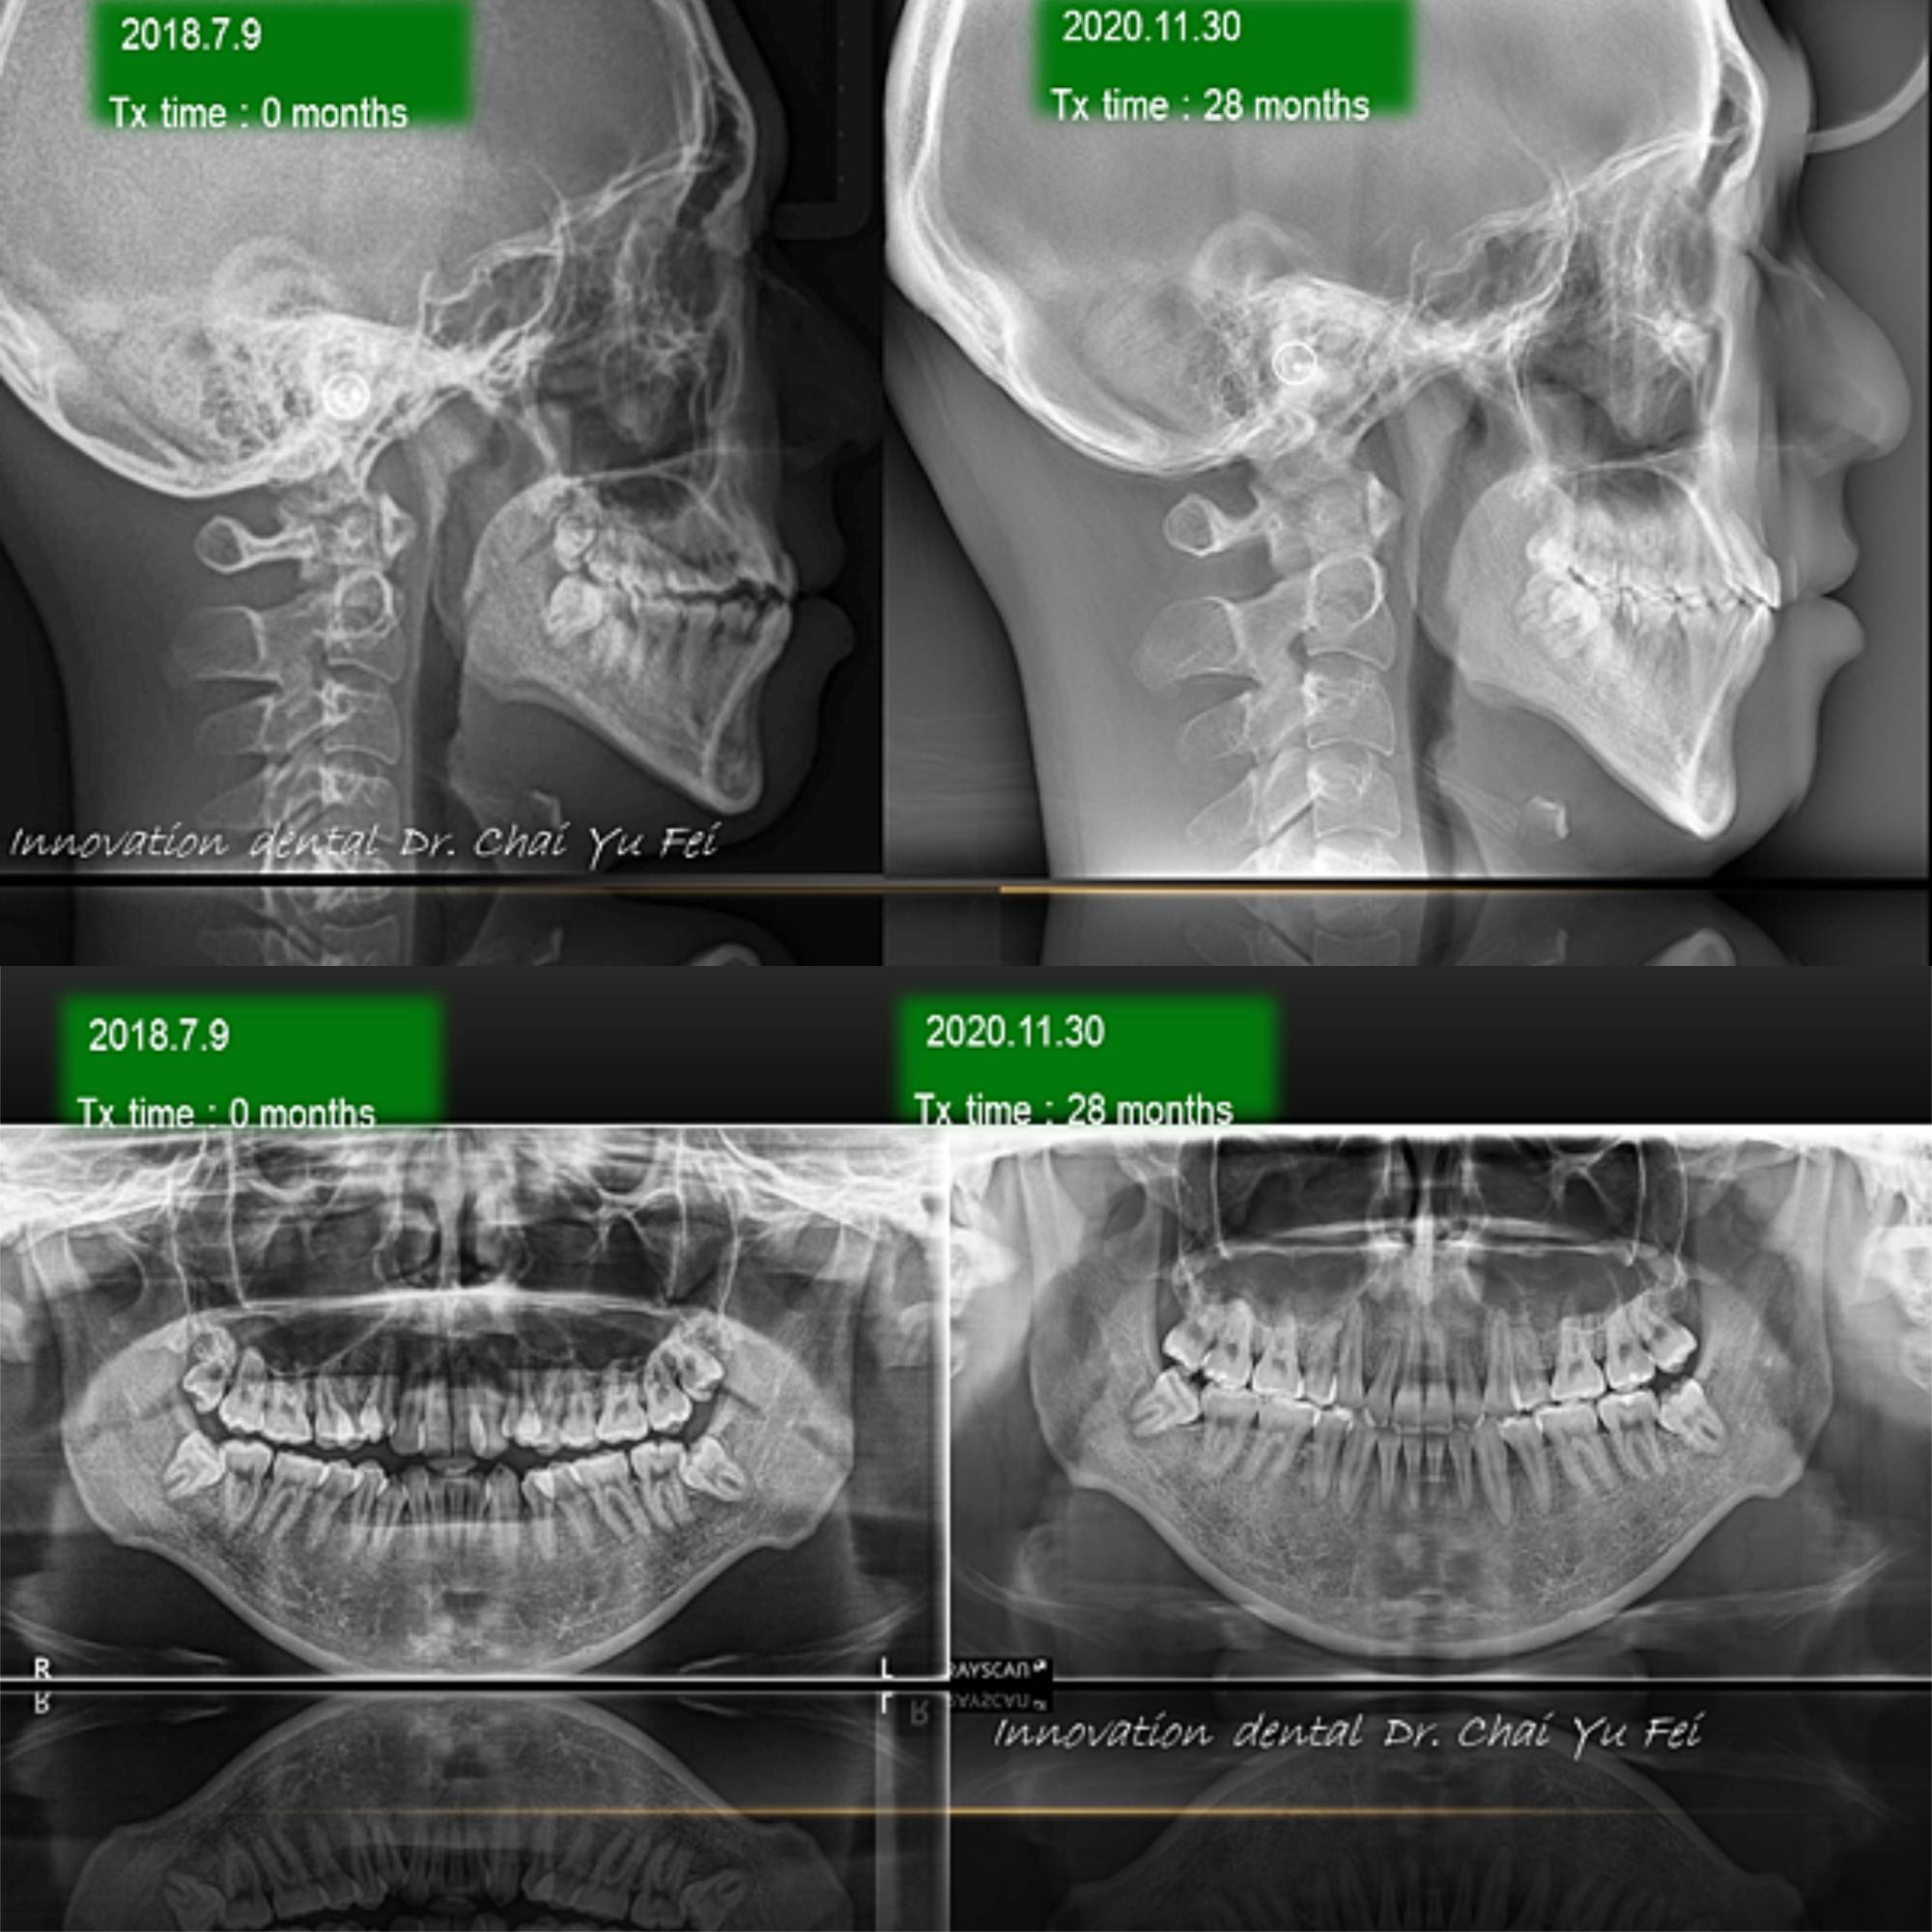

[ 治療方式 ] : 拔牙矯正 ,使用迷你骨釘 , 將上顎齒列擴張,將側門牙彈出,改善錯咬,製造完美笑容

[ 治療時間 ] : 28 個月

[ 矯正器種類 ] : ROTH 18X25 自瑣式 矯正器

矯正前上唇豐隆度較不足

由於他有輕微厚道的趨勢,上顎前牙牙弓較窄,

觀察臉型之後決定以拔牙來將上下顎擁擠改善,排出側門牙跟改善錯咬的狀況。

上顎使用2隻迷你骨釘,靠著矯正器及線的作用,去將他卡在後面的牙齒排列出來,增加上顎豐隆度。